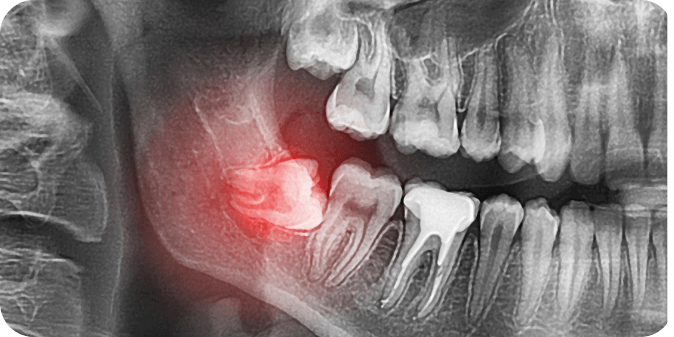

Treatment for Impacted Wisdom Teeth

The most common treatment is extracting the impacted wisdom tooth. This requires a minor surgical procedure that can be done under local or general anaesthesia.

A cut is made in the gum to remove the tooth. The tooth may be sectioned into smaller pieces depending on its position. Under local anaesthesia, you will be conscious during the procedure, but will not feel pain. While it will not hurt, you may feel some pressure, or hear cracking sounds. Sedation is also available to help you relax and remain calm.